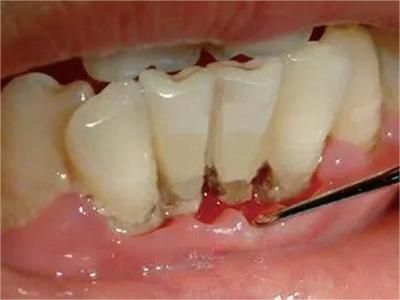

急性坏死性溃疡性龈炎起病急,病程短,常为数天至1-2周,以龈乳头和龈缘的坏死为其特征性损害,尤以下前牙多见,初起时龈乳头充血水肿,个别龈乳头顶端可发生坏死性溃疡,上覆有灰白色坏死物,中央凹下如火山口状。龈缘如虫蚀状,坏死区出现灰褐色假膜,擦去后可见出血创面。龈乳头被破坏后与龈缘成一直线,如刀切状。病损一般不波及附着龈,患处牙龈极易出血,疼痛明显并有腐败性口臭。